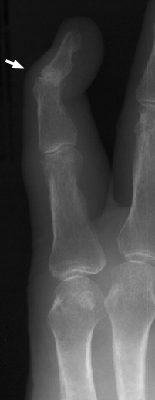

Swan Neck Deformity

Rheumatoid arthritis

Among the many osseous abnormalities that may be seen in Rheumatoid Arthritis, the swan neck deformity is the culmination of multiple abnormalities in the hand. Specifically, the deformity arises from hyperextension of the proximal interphalangeal joint, while the distal interphalangeal joint is flexed.